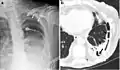

| Fibrothorax on chest x-ray | |

A fibrothorax can typically be diagnosed by taking an appropriate medical history in combination with the use of appropriate imaging techniques such as a plain chest X-ray or CT scan.[3] These imaging techniques can detect fibrothorax and pleural thickening that surround the lungs.[7] The presence of a thickened peel with or without calcification are common features of fibrothorax when imaged.[3] CT scans can more readily differentiate whether pleural thickening is due to extra fat deposition or true pleural thickening than X-rays.[3]

If a fibrothorax is severe, the thickening may restrict the lung on the affected side causing a loss of lung volume.[7] Additionally, the mediastinum may be physically shifted toward the affected side.[3] A reduction in the size of one side of the chest (hemithorax) on an X-ray or CT scan of the chest suggests chronic scarring.[6] Signs of the underlying disease causing the fibrothorax are also occasionally seen on the X-ray.[6] A CT scan may show features similar to those seen on a plain X-ray.[7] Lung function testing typically demonstrates findings consistent with restrictive lung disease.[6]

Extensive left-sided fibrothorax

Chest radiograph displaying inhomogeneous opacification of the left half of the chest that is fibrothorax